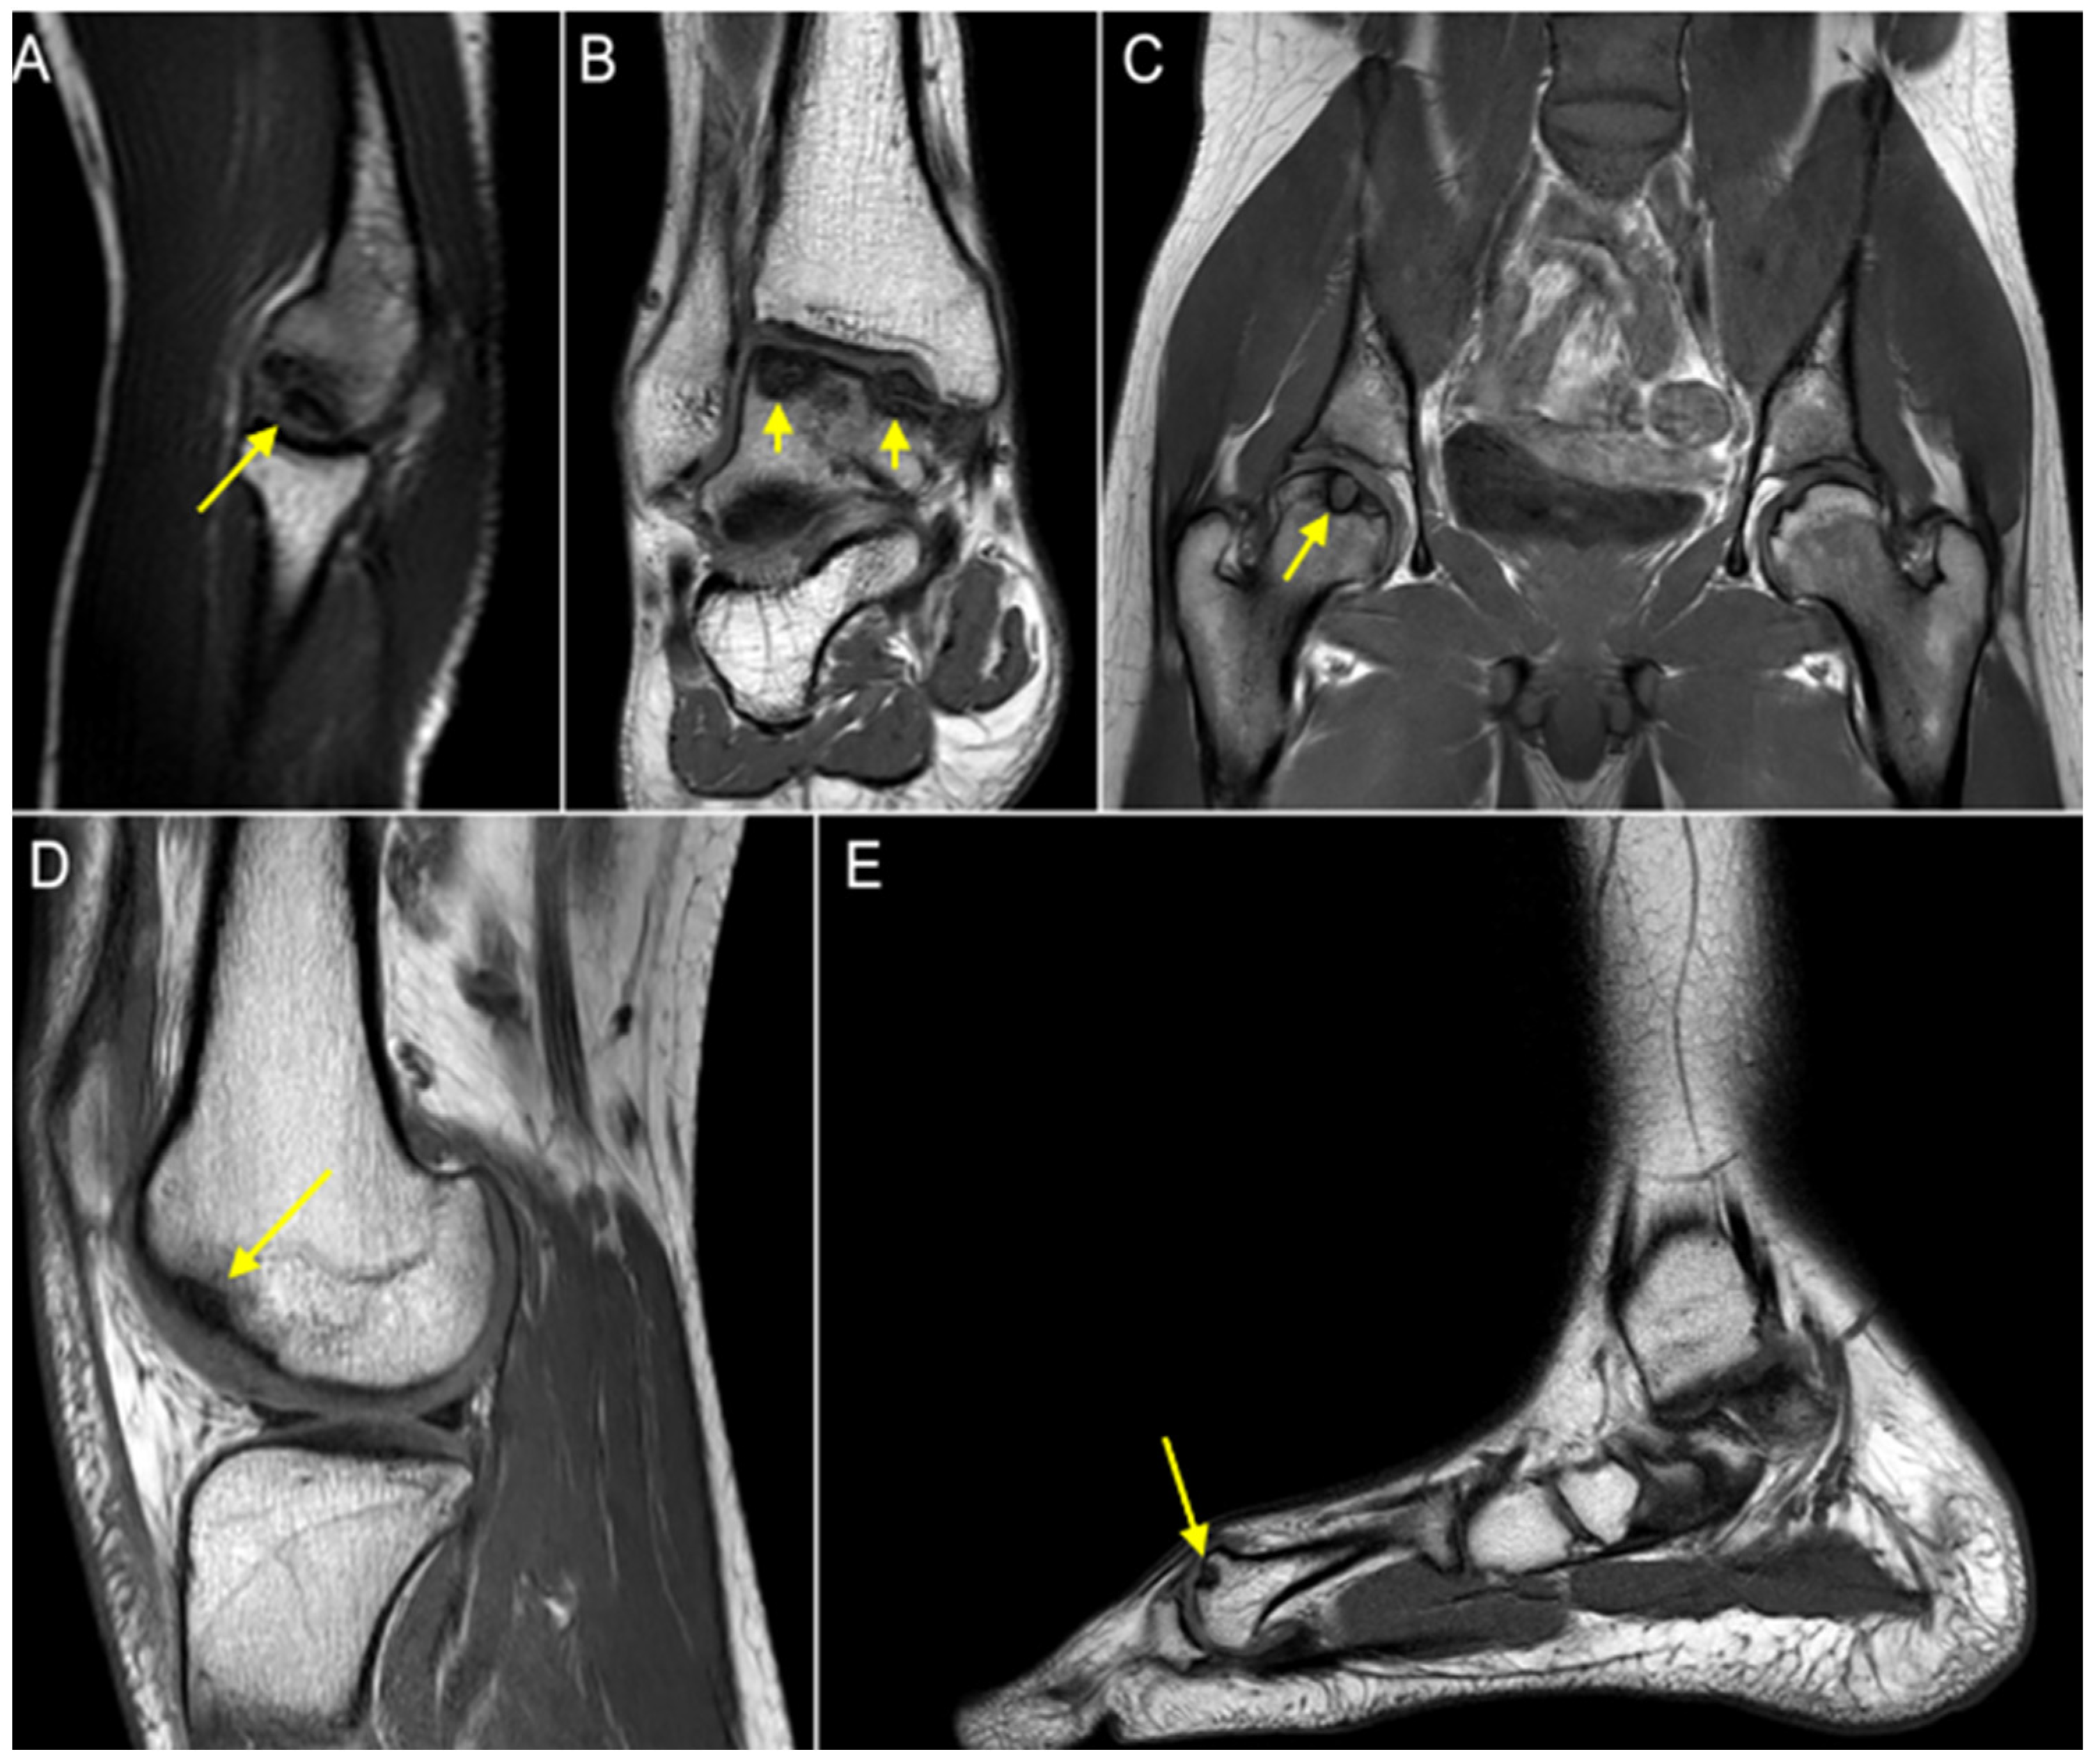

When he was 20 years old, a radiological evaluation due to right elbow pain revealed OCD of the capitellum (Figure 2A). Further imaging investigation showed OCD also at the ankles, bilaterally. At the age of 21 years, he had his right ankle treated arthroscopically with symptom resolution (Figure 2B). One year later, he underwent a right hip core decompression for OCD (Figure 2C), referring to temporary benefit after the surgery. In addition, the patient was assessed by a total-body MRI, which showed asymptomatic distal right femur (Figure 2D) and left first metatarsal OCD (Figure 2E).

To summarize, at 21 years old, the patient had multiple OCD diagnoses of the right elbow, right distal femur, right hip, bilateral ankles, and left first metatarsal.

Figure 2. (A) OCD of the capitellum; (B) OCD of the right talus; (C) OCD of the right hip; (D) OCD of the right knee; (E) OCD of the left first metatarsal. Arrows indicate OCD sites.